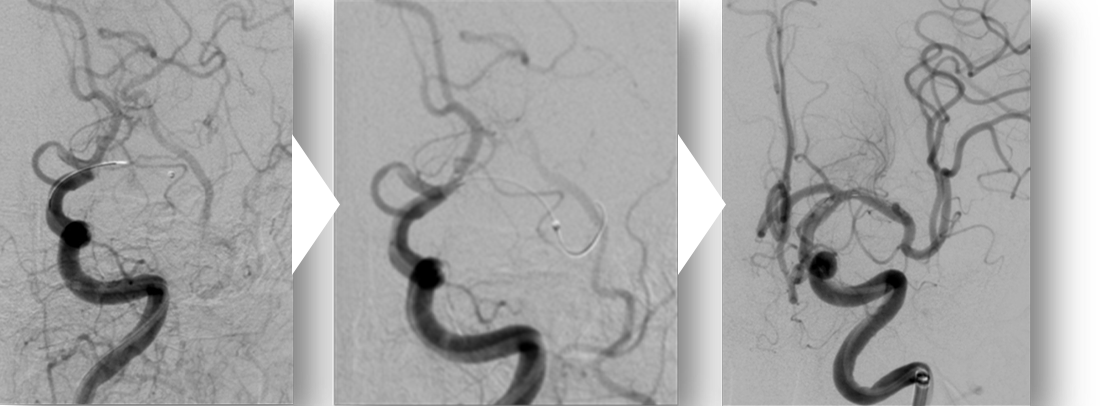

このように大血管が詰まってしまった場合には、一刻も早く血管を再開通させることが必要です。

再開通の方法には、tPA(ティーピーエー)という点滴薬による血栓溶解治療や、カテーテルという細い管を血管に通して血栓を取り除く治療(機械的血栓回収療法)があります。血栓溶解薬治療は多くの病院で受けることができるようになりましたが、機械的血栓回収療法はいまだ受けられる病院が限られており、熊本県内でも数施設にとどまっています。